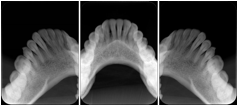

3. A dental provider wishes to capture a series of DICOM IO images for the patient’s dentition. The tooth morphology, teeth are divided into molars, premolars, canines and incisors, and a number of images for each jaw. The anatomic information was captured utilizing the triplet of schema. This standard code sequence is based on ISO 3950-2010, Dentistry - Designation system for teeth and areas of the oral cavity.

Every IO image should have anatomic information either through the primary or modifier sequence.

In most standard cases, images are oriented in structured layouts. These structured displays are useful to be shared between providers for reference purposes.

Table OO.1.1-1 shows structured display standard templates, where Viewset ID is based on the Japanese Society for Oral and Maxillofacial Radiology (JSOMR) classification provided by JIRA (Japan Medical Imaging and Radiological Systems Industries Association, www.jira-net.or.jp). Expected or typical teeth to be imaged location, region and designation codes are based on ISO 3950-2010, Dentistry - Designation system for teeth and areas of the oral cavity. For all the hanging protocols listed in OO.1.1-1, the value to use for Hanging Protocol Creator (0072,0008) is "JSOMR" and the value to use for Hanging Protocol Name (0072,0002) does not include "JSOMR" (e.g., "DL-S001A", not "JSOMR DL-S001A").